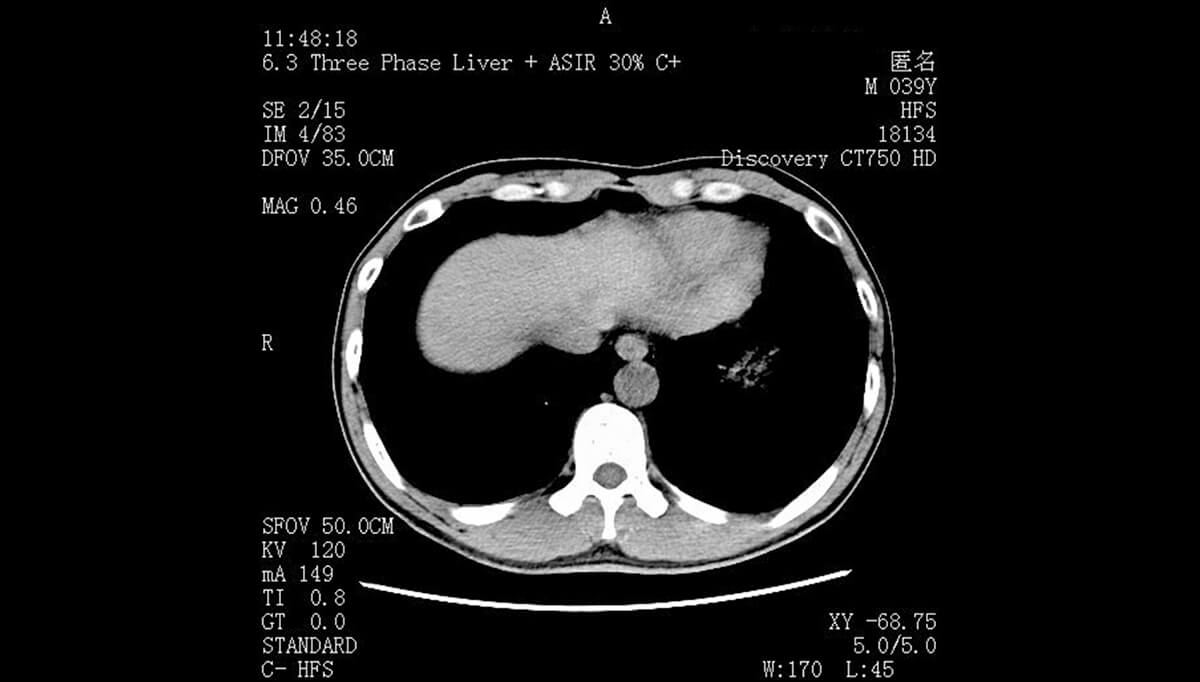

临床诊疗场景中,医疗一体机的创新应用尤为突出。在门诊诊室,具备高清触控与多模态显示功能的医疗一体机,可同步呈现患者电子病历、影像报告、检查数据,医生通过触控操作即可完成信息调取、诊断标注,大幅缩短诊疗流程;在手术室,高分辨率、抗干扰的医疗一体机显示器可实时显示手术导航影像、患者生命体征数据,为精准手术提供可视化支撑。此外,搭载AI辅助诊断模块的显示器,能将AI分析结果与原始医疗数据同屏展示,辅助医生提升诊断效率与准确率。